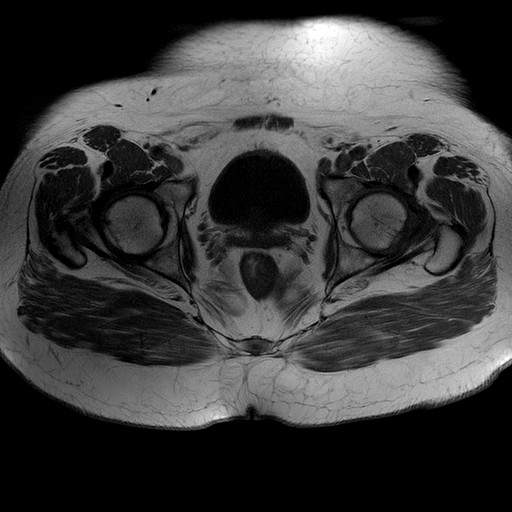

Esami: RMN BACINO

T1W_TSE

Evidenti e simmetriche alterazioni osteofitosiche in regione coxo femorale con riduzione delle rime articolari. Degenerazione completa del cercine glenoideo. Non attuali segni di versamento articolare. Non segni di edema osseo che escludono attuale algodistrofia od osteonecrosi. Lieve e simmetrica riduzione del trofismo della muscolatura glutea.